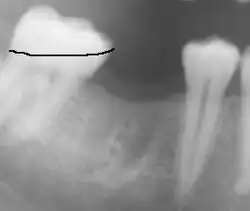

Um eine gemeinsame Einschubrichtung für die Halteelemente einer Teilprothese zu bestimmen, kann der prothetische Zahnäquator bei Zahnkippungen erheblich vom anatomischen abweichen.

Zur Bestimmung des prothetischen Zahnäquators werden die Zähne mit einem Parallelometer exakt vermessen und der Zahnäquator angezeichnet. Der Bereich unterhalb des Zahnäquators wird als Infrawölbung, der oberhalb des Zahnäquators als Suprawölbung bezeichnet. Nur der Infrabereich der Zähne kann einer Prothese den nötigen Halt geben.